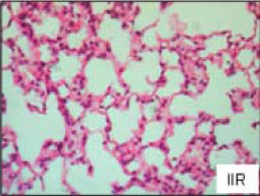

The key pathological features of human ALI/ARDS are a severe neutrophilic alveolitis with deposition of hyaline membrane and formation of microthrombi (Figure 1). It is important to emphasize what each of the components of the ALI/ARDS pathologic triad indicates:

Figure 1. Human ARDS

Note the severe intra-alveolar infiltrates, deposition of hyaline membranes, vascular congestion and microthrombi.